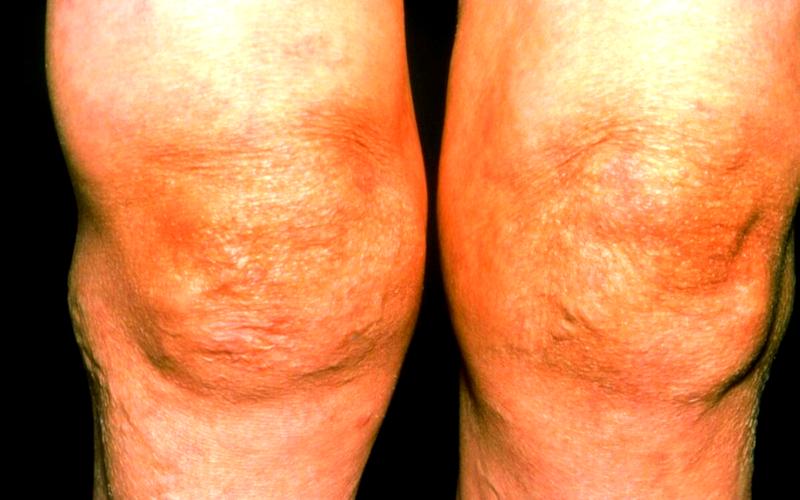

人到中老年,不少人會被膝關節骨性關節炎纏上——上下樓梯時膝蓋“咔咔”響,蹲起時鉆心疼,嚴重時連平地走路都成了難題。臨床上,關節沖洗聯合玻璃酸鈉、糖皮質激素注射是常用的治療手段,尤其適合癥狀較明顯的膝關節痛患者。但這種治療并非人人適用,利弊需要掰扯清楚,才能幫膝蓋選對治療方案。

當膝關節骨性關節炎發展到中度,出現明顯腫脹、疼痛、活動受限,且口服藥物效果不佳時,醫生常會建議關節沖洗+玻璃酸鈉+糖皮質激素聯合治療,我們先說說這種療法的“利”:

膝關節骨性關節炎